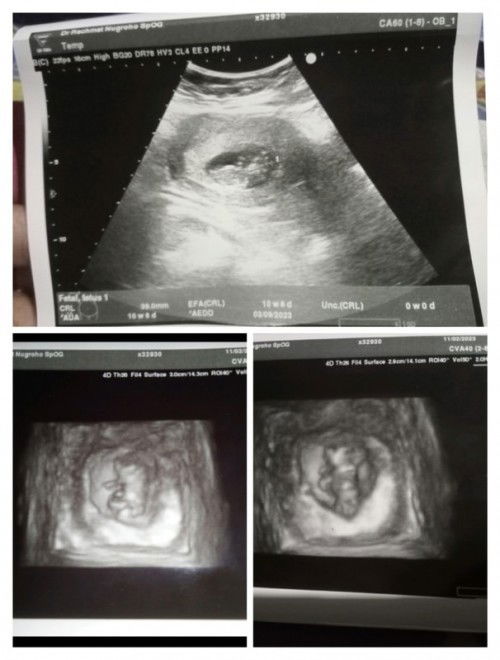

Hasil USG 10 Minggu 6 hari kok beda ya usia nya sama aplikasi saya 10 Minggu 1 hari.

Mau tanya bun itu gimana hasil baca USG nya ya soal nya dokter nya gak jelasin Bun sedetailnya cuma bilang normal semua . Maskd nya CRL 39.0mm itu normal aja kah Bun di usia segini Tolong bantuannya bun Kok berubah ya perkiraan lahir nya dri USG pertama kmren ini tgl 03-09-23 tgl 19 kmren sya USG pertama perkiraan nya tgl 15-09-23